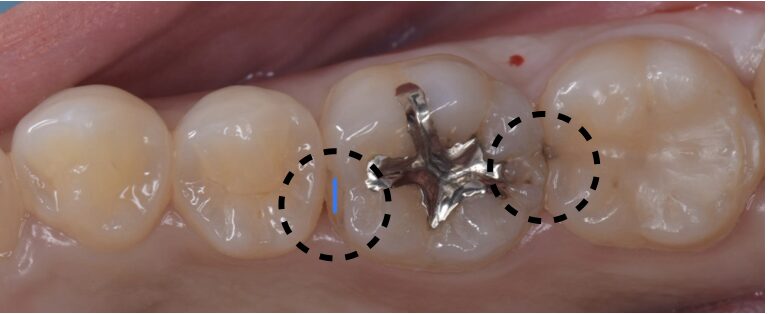

銀歯の虫歯治療(セラミックインレー)

Before

After

30代 女性

点線のところに虫歯が認められました。

虫歯を除去後、型取りを行いました。

セラミックインレーセット。

治療回数は2回で終了。